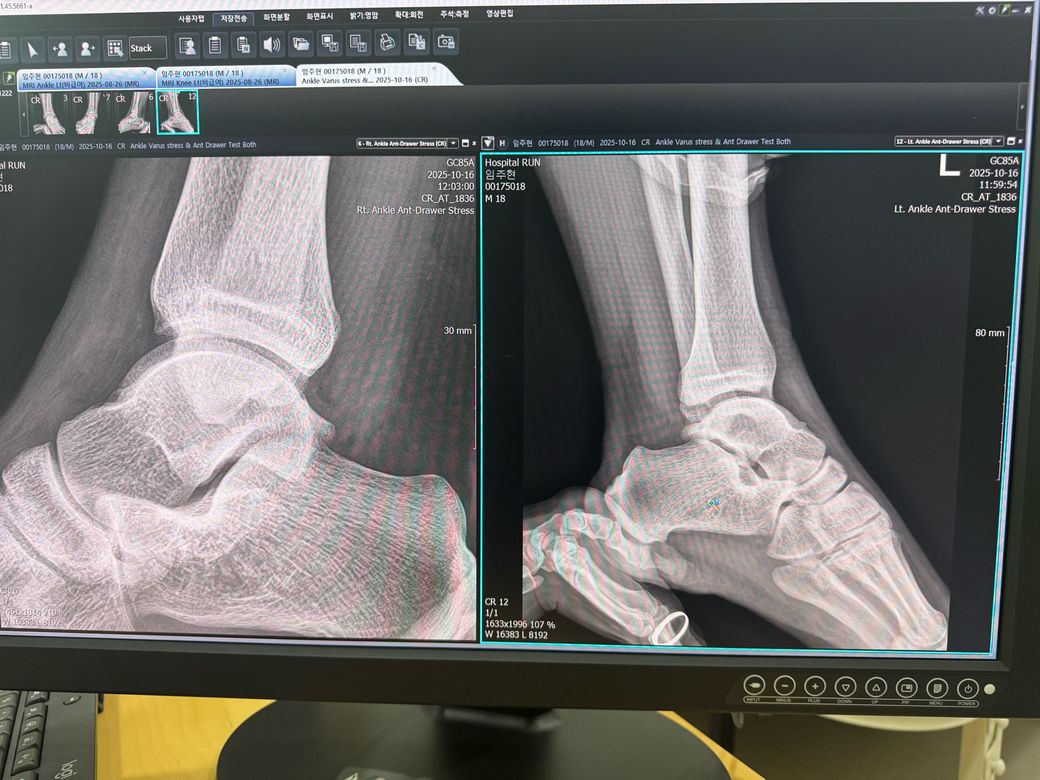

오늘 엑스레이를 찍어보니 왼쪽이

이렇게 심해서 내년에 인대재건술을 하자고 하시는데

엑스레이상 왼쪽 발목의 불안정성이 꽤 심한 편이라면, 인대 재건술 후에는 회복 기간이 깁니다. 보통 수술 후 6개월은 안정과 재활에 집중하고, 운동을 하려면 그 이상 걸릴 수 있습니다. 다만 현역 판정 여부는 실제 진단서, MRI 결과, 수술 여부 등에 따라 달리지므로 병무청 지정 병원에서 별도 판정을 받아야 합니다.